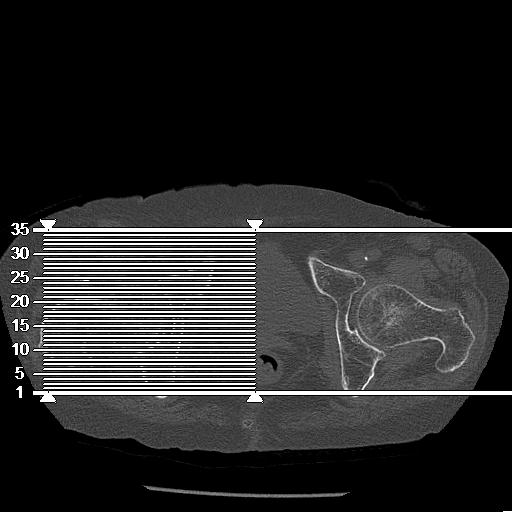

56476 8/28 4R 1/21 2R 左足関節 デジカメ写真 72歳女性 右足関節AS